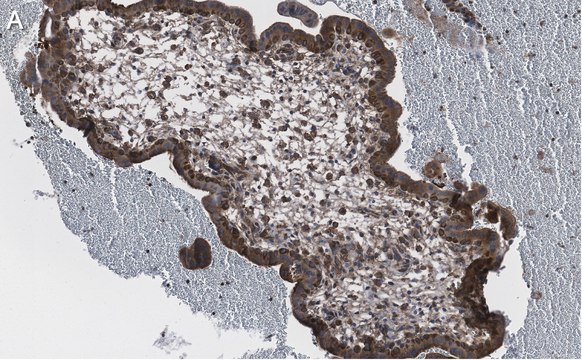

Immunohistochemistry (Paraffin) Analysis: A 1:100 dilution from a representative lot detected NF-kB p65 subunit in human placenta tissue sections.